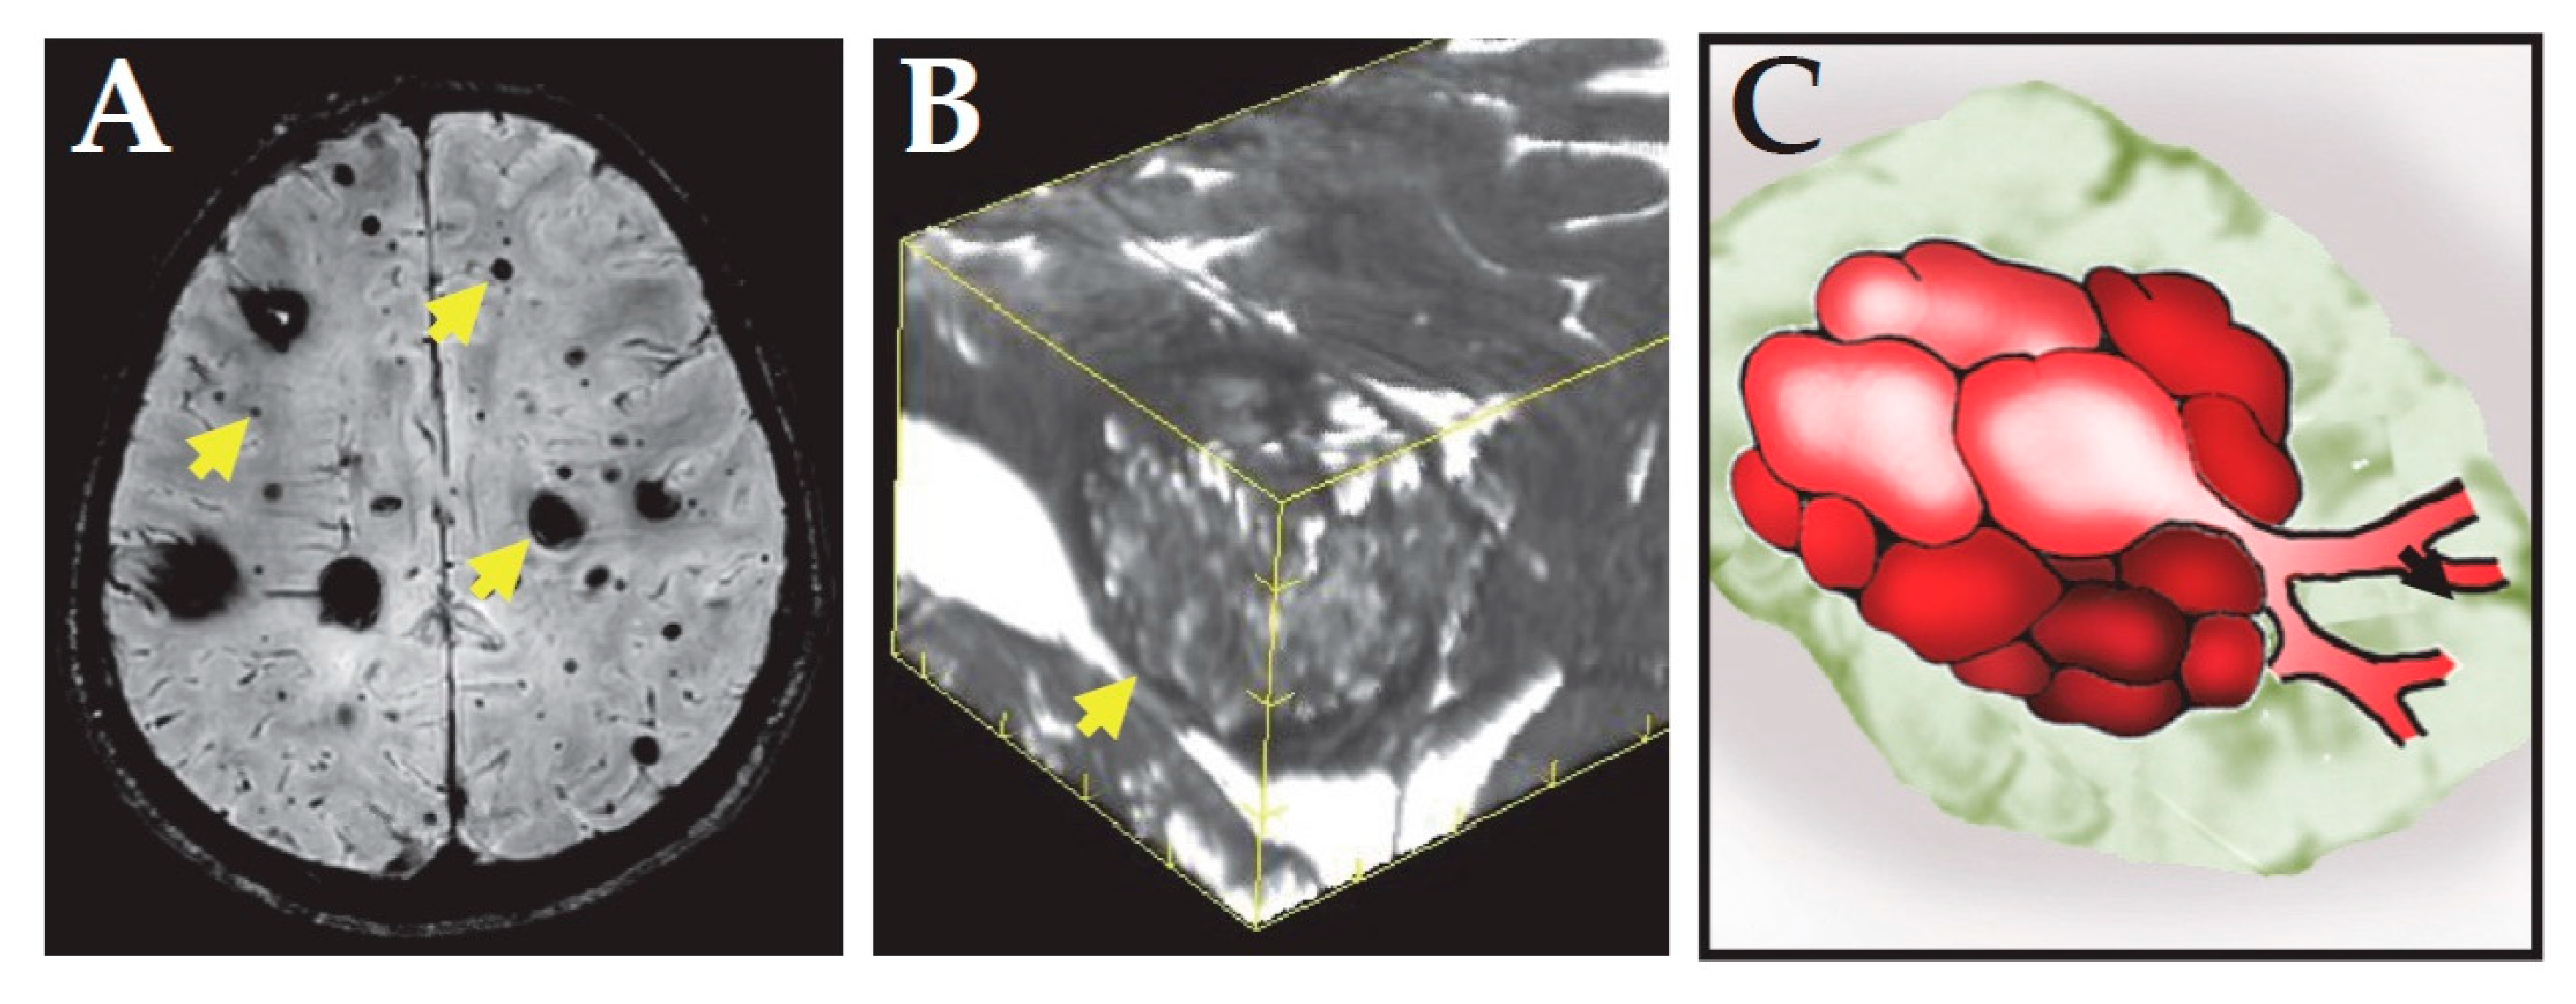

- Wong, J.H.; Awad, I.A.; Kim, J.H. Ultrastructural pathological features of cerebrovascular malformations: A preliminary report. Neurosurgery 2000, 46, 1454–1459. [Google Scholar] [CrossRef] [PubMed]

- Tu, J.; Stoodley, M.A.; Morgan, M.K.; Storer, K.P. Ultrastructural characteristics of hemorrhagic, nonhemorrhagic, and recurrent cavernous malformations. J. Neurosurg. 2005, 103, 903–909. [Google Scholar] [CrossRef]

- Girard, R.; Fam, M.D.; Zeineddine, H.A.; Tan, H.; Mikati, A.G.; Shi, C.; Jesselson, M.; Shenkar, R.; Wu, M.; Cao, Y.; et al. Vascular permeability and iron deposition biomarkers in longitudinal follow-up of cerebral cavernous malformations. J. Neurosurg. 2017, 127, 102–110. [Google Scholar] [CrossRef]

- Mikati, A.G.; Khanna, O.; Zhang, L.; Girard, R.; Shenkar, R.; Guo, X.; Shah, A.; Larsson, H.B.; Tan, H.; Li, L.; et al. Vascular permeability in cerebral cavernous malformations. J. Cereb. Blood Flow Metab. 2015, 35, 1632–1639. [Google Scholar] [CrossRef]